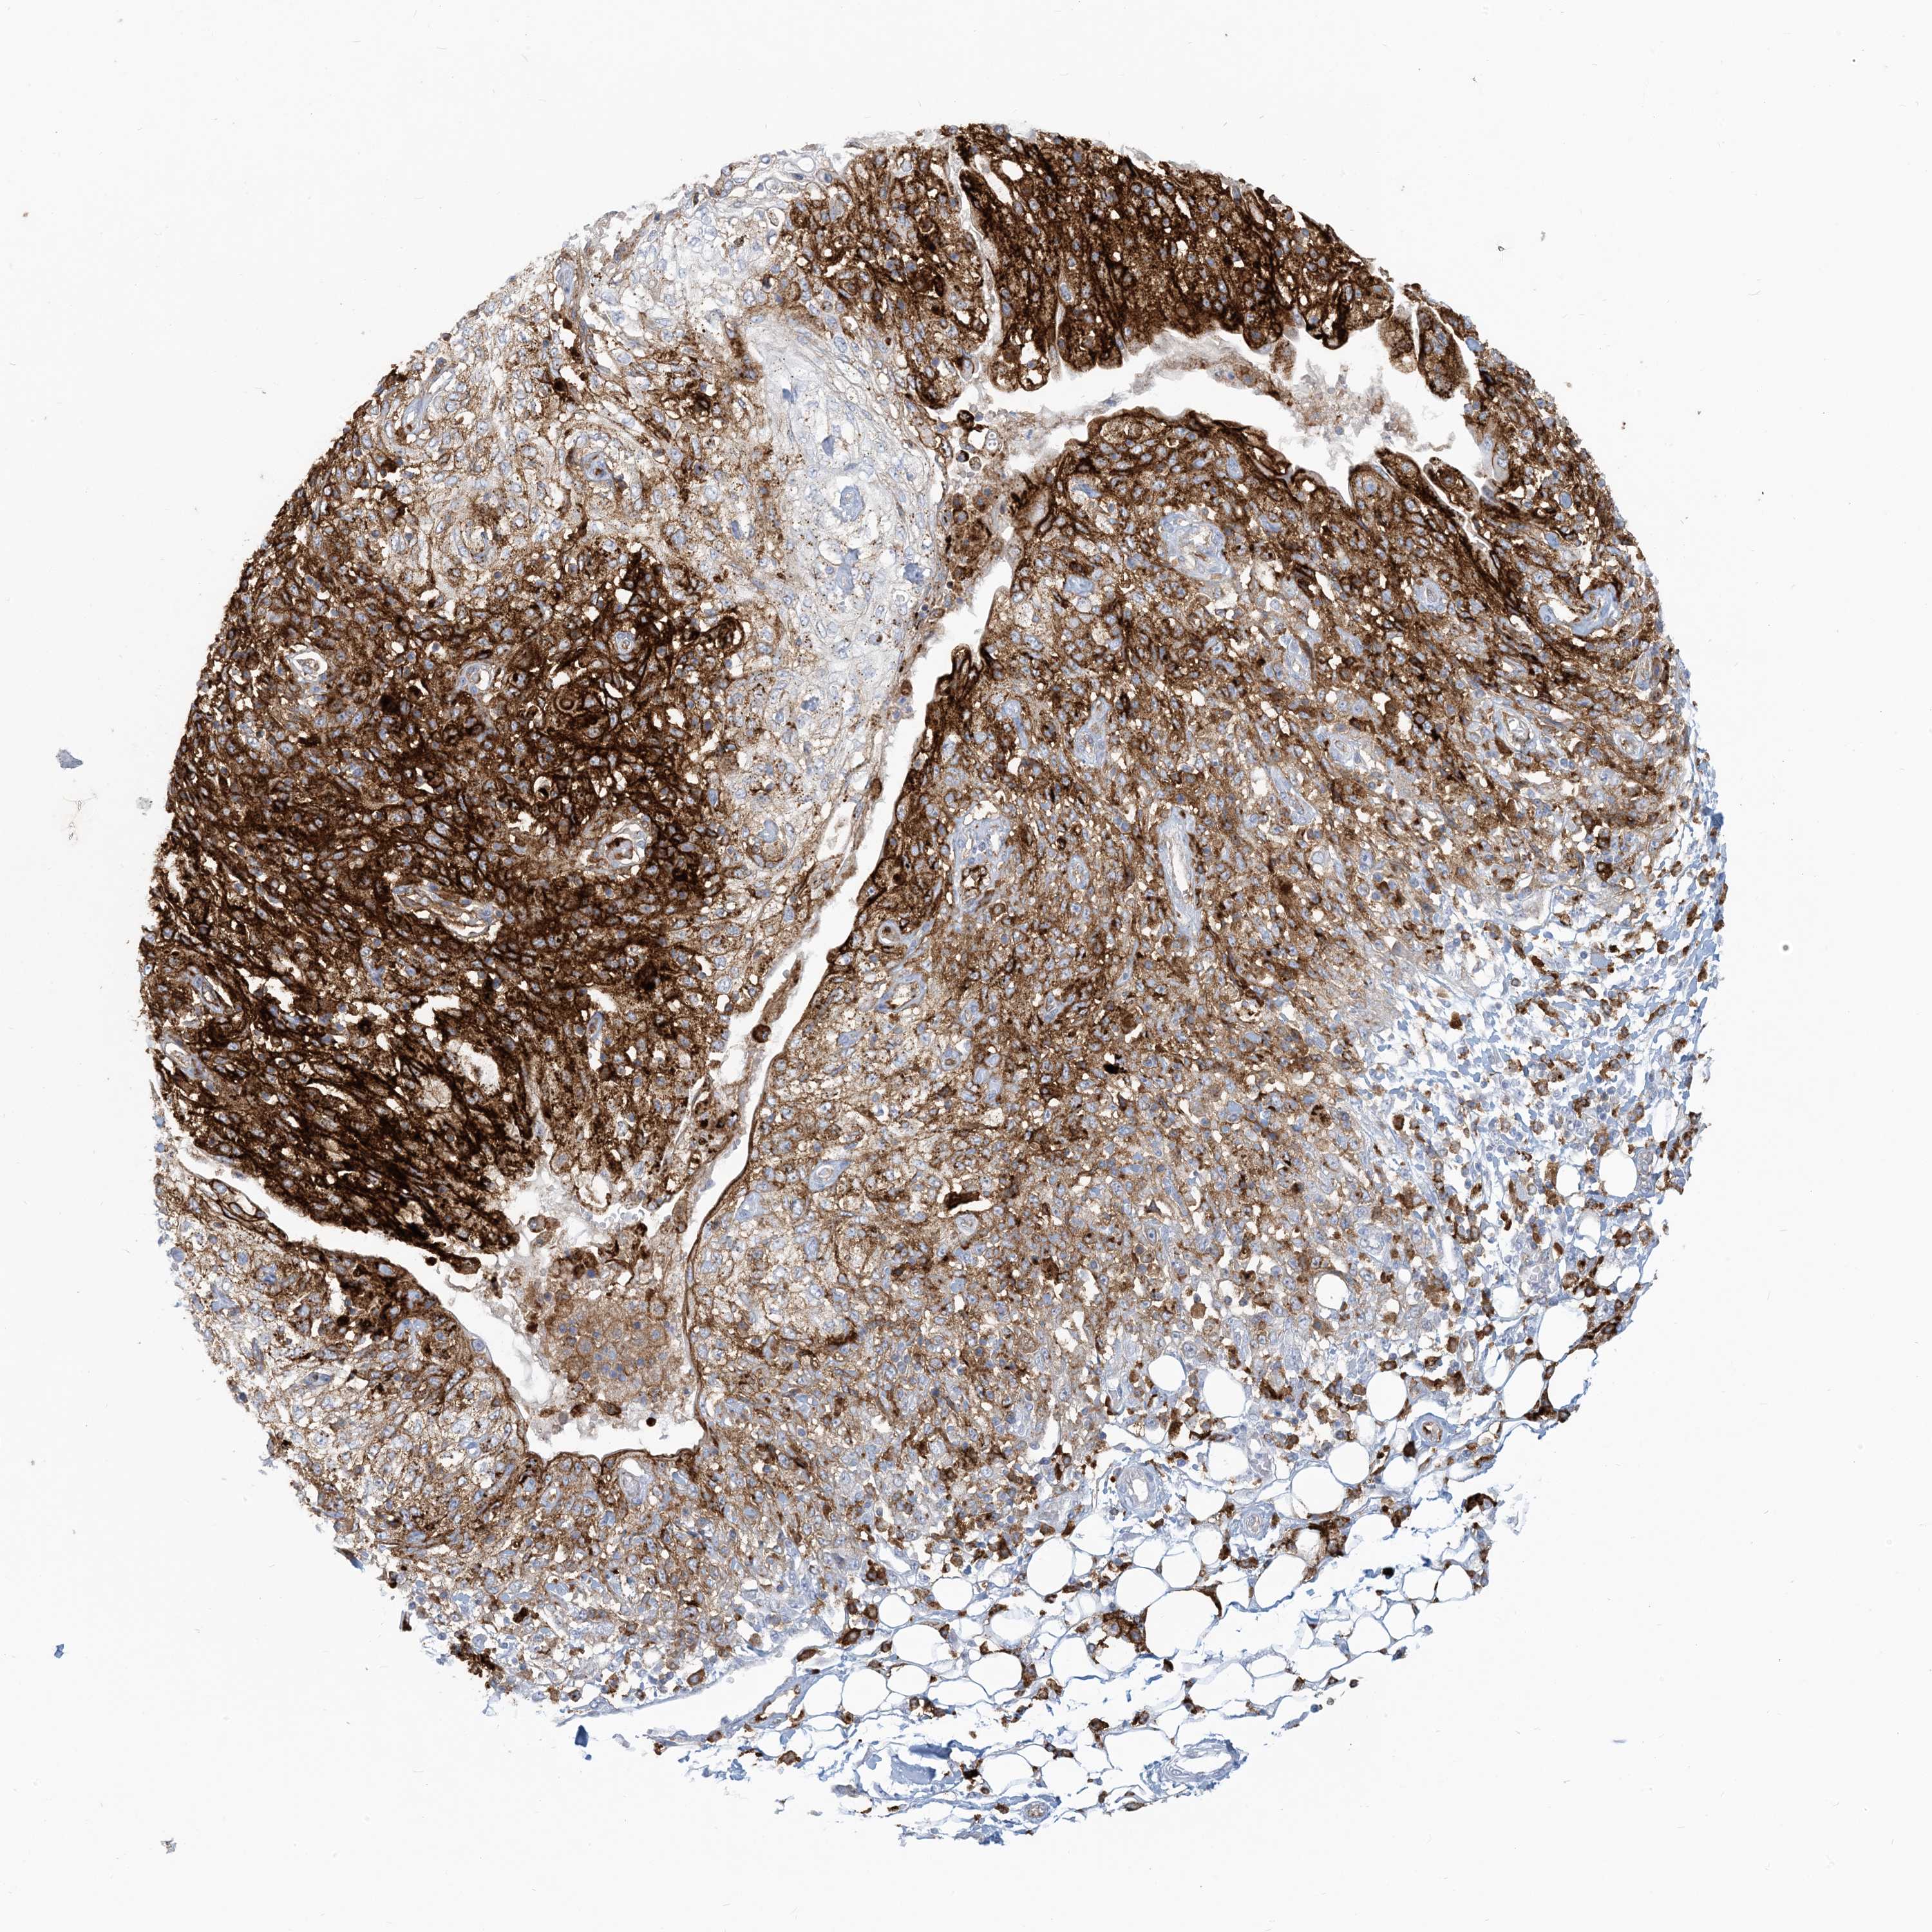

SKIN CANCER - Protein expressioni

A mouse-over function shows sample information and annotation data. Click on an image to view it in a full screen mode. Samples can be filtered based on level of antibody staining by selecting one or several of the following categories: high, medium, low and not detected. The assay and annotation is described here.

Antibody staining in the annotated cell types in the current human tissue is reported as not detected, low, medium, or high, based on conventional immunohistochemistry profiling in selected tissues. This score is based on the combination of the staining intensity and fraction of stained cells.

Each image is clickable and will lead to virtual microscopy that enables deeper exploration of all samples and also displays staining intensity scores, fraction scores and subcellular localization as well as patient and tissue information for each sample.

Antibody CAB034021

Squamous cell carcinoma, metastatic, NOS

Squamous cell carcinoma, NOS